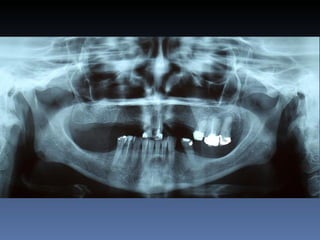

Dominga Maria silva

Idade – 53 anos

Sexo – Feminino

Raça – Caucasiana

ASA – II

Data- 23-04-2012

Diagnóstico:Desdentada parcial maxila

Plano de tratamento:      Reabilitação com 6 blocos

“onlay” provenientes de Úmero fresco-congelado

(FFB); reabertura para instalação de 6 implantes

dentários endo-ósseos e reabilitação protética fixa.

22-09-2011

20-04-2012

OPG Pré-op